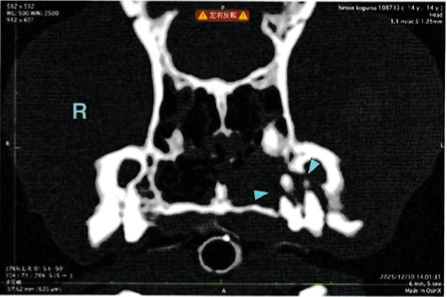

今回の症例は、くしゃみを主訴に来院されました。歯周病以外の疾患の除外と、歯周病箇所の場所の特定のため、CT検査を行いました。

左の上顎第1〜3前臼歯が鼻腔とつながっていることがわかったため、歯科処置にて、抜歯とフラップ形成を行いました。